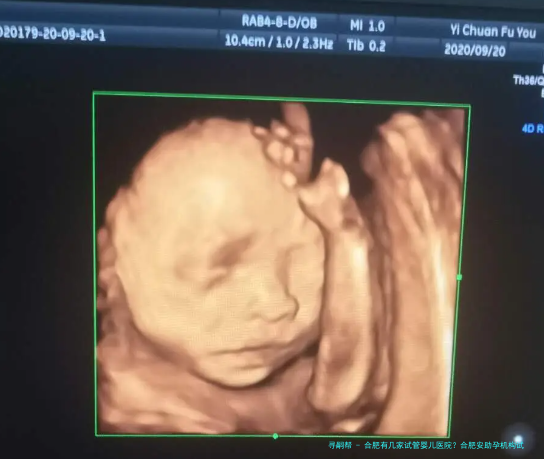

在合肥想做试管婴儿的夫妻越发越多。好在合肥能做试管婴儿的医院有许多,目前合肥有四家医院可以选择。面对合肥4家可以做试管婴儿的医院,很多夫妻会问合肥哪家医院好?在合肥做试管婴儿的费用是几许?接下来让我带所有人一起了解一下吧!

导致夫妻出现试管助孕的要素是越来越多,无数病患都是经过无数次的治疗后,仍旧没有自行受孕,以至于最终才抉择了试管婴儿,把最后的期望都寄与在试管婴儿技术上。试管婴儿一直同是备受注意的问题,尤为是试管婴儿医院和试管婴儿的成功率,网上对试管婴儿的表述真是众说纷纭。随着试管婴儿的普遍应用,很多医院也都展开了辅助生殖技术,这同样是试管婴儿进补的一个别现。